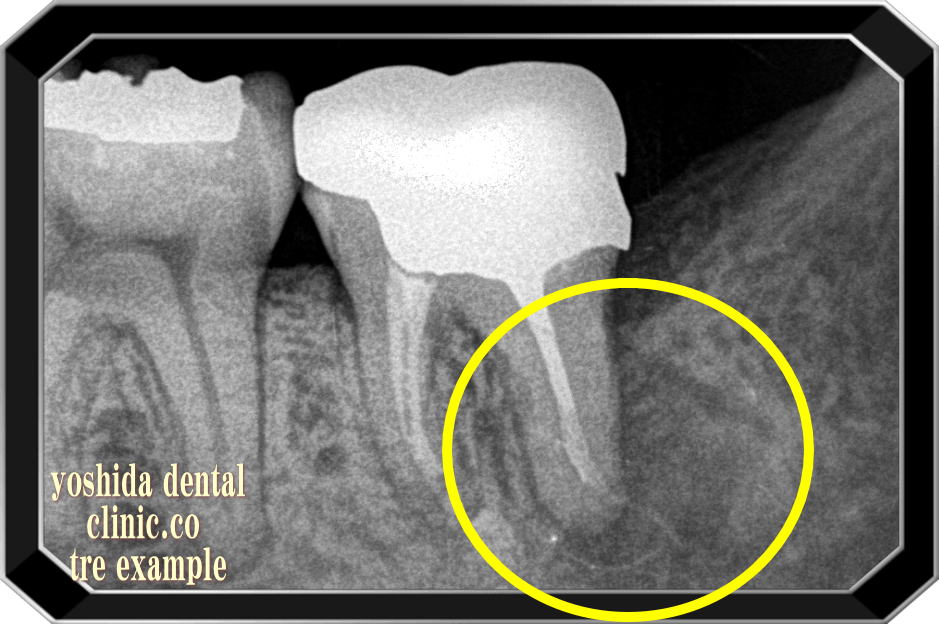

NI-TIファイルを用いた保険による根管治療前・後

根尖病変 R→ 根尖病変改善

根管治療前 根管治療後の骨再生

根の先の炎症で骨が溶けています(黒くなっている部分)。あなたならどうしますか?

抜歯されますか?根の治療を保険治療で行い保存されますか?

当院での保険治療後右の写真では骨が治癒し白さ(骨)を取り戻しています。

~全症例マイクロスコープは使用していません~

~保険にて根管の治療を行って治癒しています~